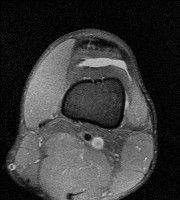

무릎 mri 간단히 봐주실 수 있으시나요 ㅠㅠ

안녕하세요 8년전 십자인대 수술하고 최근 무리한 운동에 무릎 불편감이 생겨서

mri 찍었습니다.

진단결과는 첫 찍은 병원에서 활액막염 이라는 진단을 받았습니다. 혹시 봐주실 수 있으실까요?

올라온 MRI가 단편적이라서 정확한 진단에 어려움이 있지만 십자인대에는 큰 이상이 있지는 않은것 같으며, 무릎관절내 물이 있는 것으로 보아 활액막염의 진단이 맞을 것 같습니다.

하지만 단편적인 영상이기 때문에 촬영병원에서 정확한 판독지 등을 받으시는 것이 좋겠습니다.